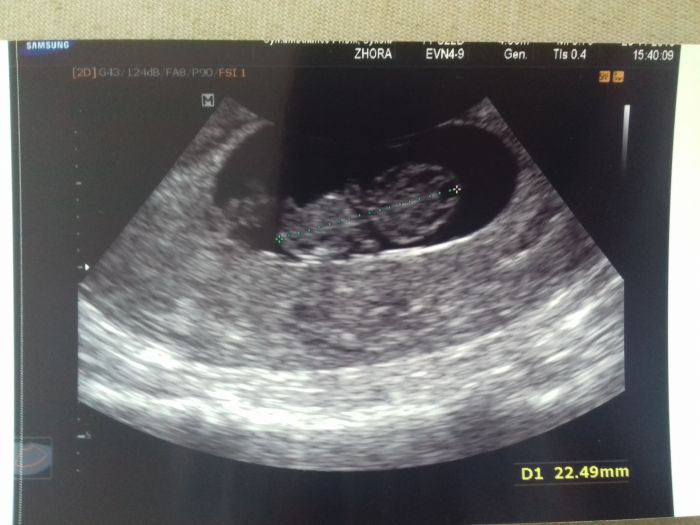

Holkyyy, dneska kontrola a na jedničku

srdíčko bije, velikost odpovida 8+5, mám průkazku a brali mi krev...Ta vůbec nechtěla téct, ale něco ze me sestra vytáhla

přikládám fotecku mimiša